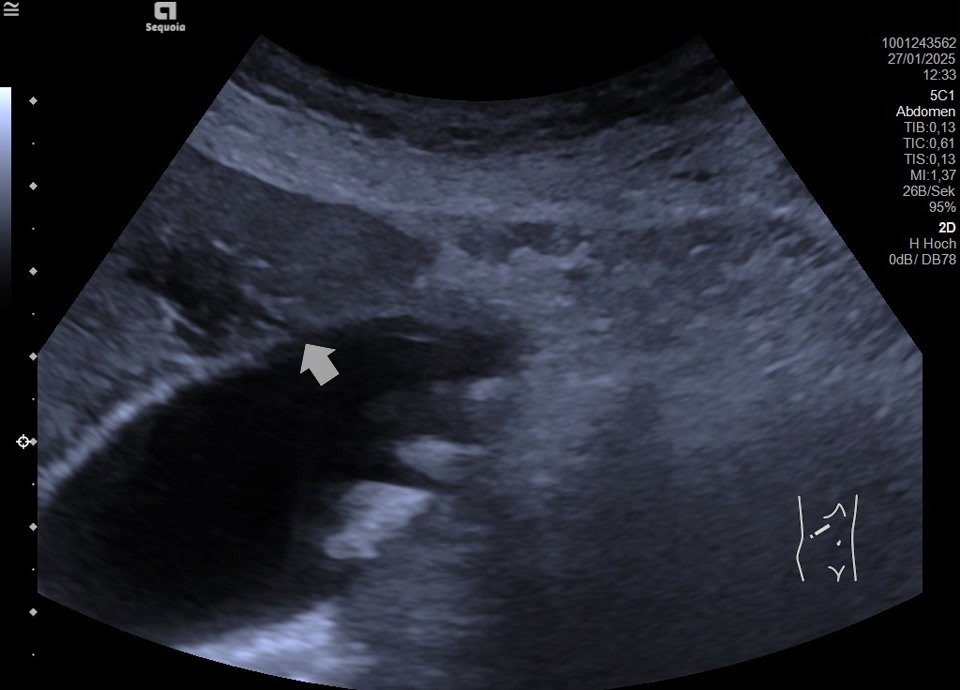

Akute Cholezystitis

Akute Cholezystitis (Wand verdickt und geschichtet), zusätzlich Gallenblasenstein im Fundus